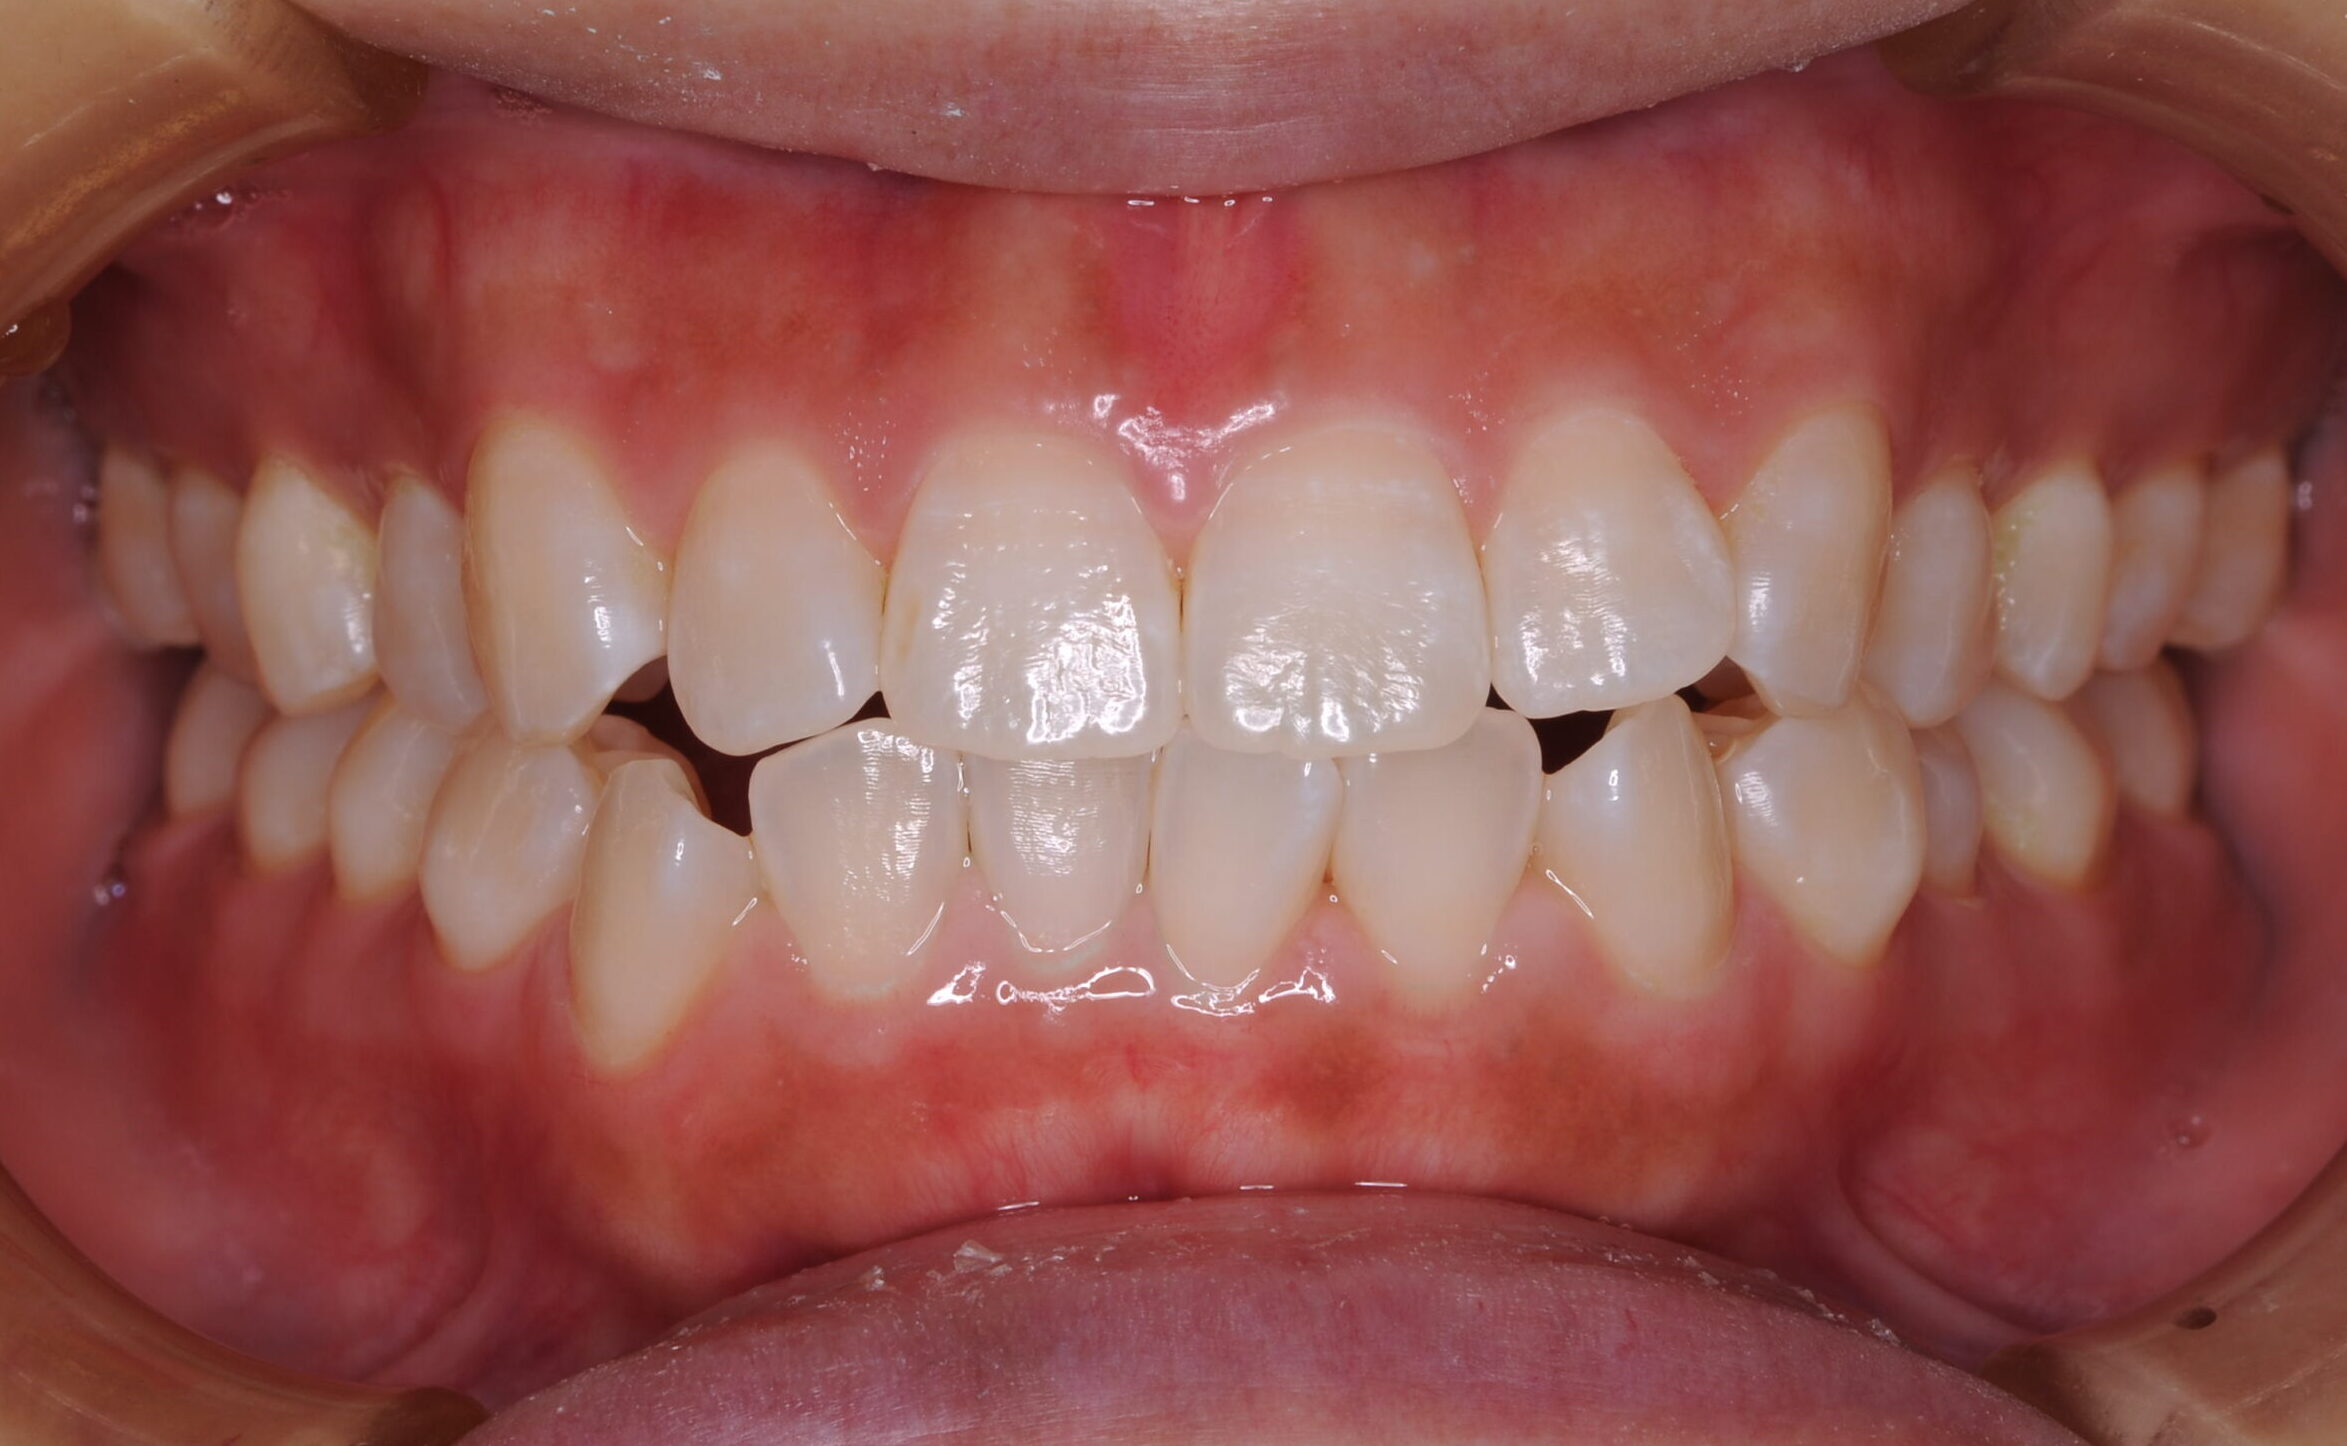

症例写真 before